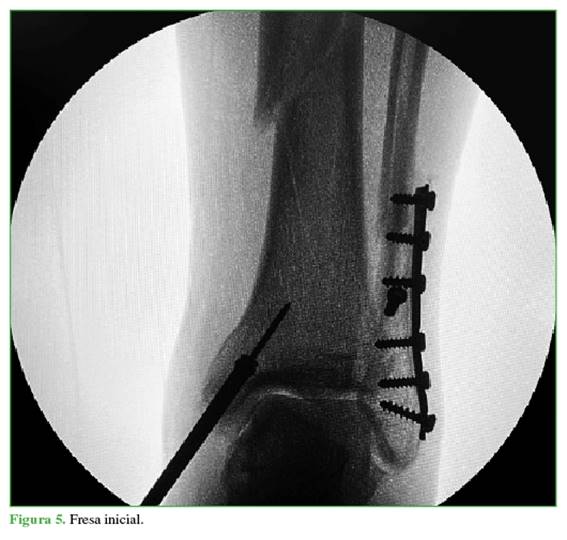

A continuación, se crea un abordaje de 3 cm desde la punta de maléolo tibial hacia distal (Figura 2). Mediante una clavija se ubica el sitio de ingreso en el centro del maléolo tibial, en ambos planos (Figuras 3 y 4), para luego agrandar con una fresa canulada la zona de ingreso (Figura 5), después se coloca una guía olivada (Figura 6) y, a través de un protector de partes blandas, se fresa el canal medular (Figura 7).